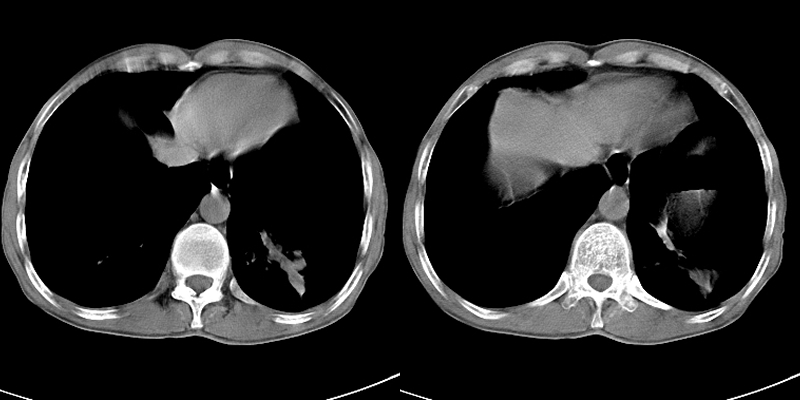

以下是引用zsl6918在2009-2-7 7:38:00的发言:[br]恶性度极高的肺癌,肺门及纵隔淋巴结转移。

以下是引用余辉在2009-2-7 8:29:00的发言:[br]考虑左下肺周围型肺癌伴肺门、纵隔淋巴转移及右肺转移